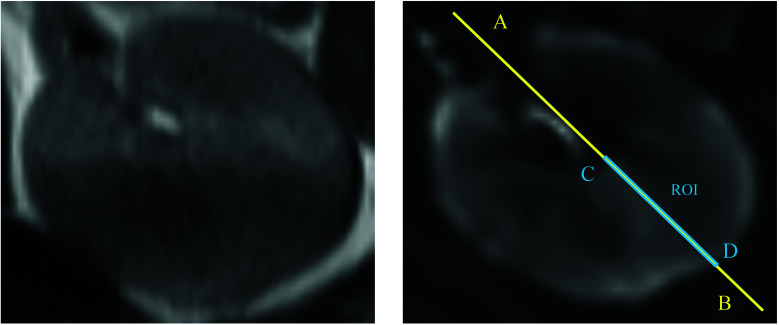

Methods: Children under 16 years of age diagnosed with mesangial proliferative glomerulonephritis by kidney biopsy at our university hospital between January 2013 and September 2022 were included in this study. Cortical and medullary spin relaxation rate (R2*) values were measured using BOLD MRI at 3T within two weeks before and after the kidney biopsy. The R2* values, including the fluctuations with low-dose oxygen administration, were retrospectively examined in relation to the cortical (mesangial proliferation, endothelial cell proliferation, crescent, sclerosis, and fibrosis) and medullary findings (fibrosis).